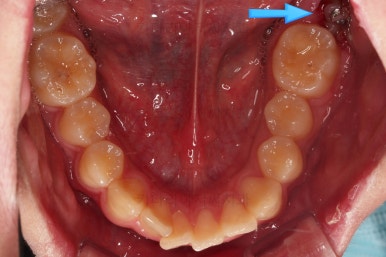

구멍이 뻥 뚫린게 보이실 거에요.

매복 사랑니를 발치한 자리인데요.

사랑니를 발치하며 앞쪽에 살려 써야하는 어금니에 작은 장치를 부착했어요.

어금니를 당겨줄 미니스크류도 사랑니를 발치하면서 식립해 주었어요.

사랑니 뽑은 자리가 매우 커 보이는데요.

보통은 3~6개월 지나면 뼈가 차오른답니다.

매복 치아였기 때문에 입 안에서는 장치도 거의 보이질 않죠.

해당 장치와 미니스크류 사이에 교정용 고무줄을 연결하여 지속적으로 당겨줍니다.